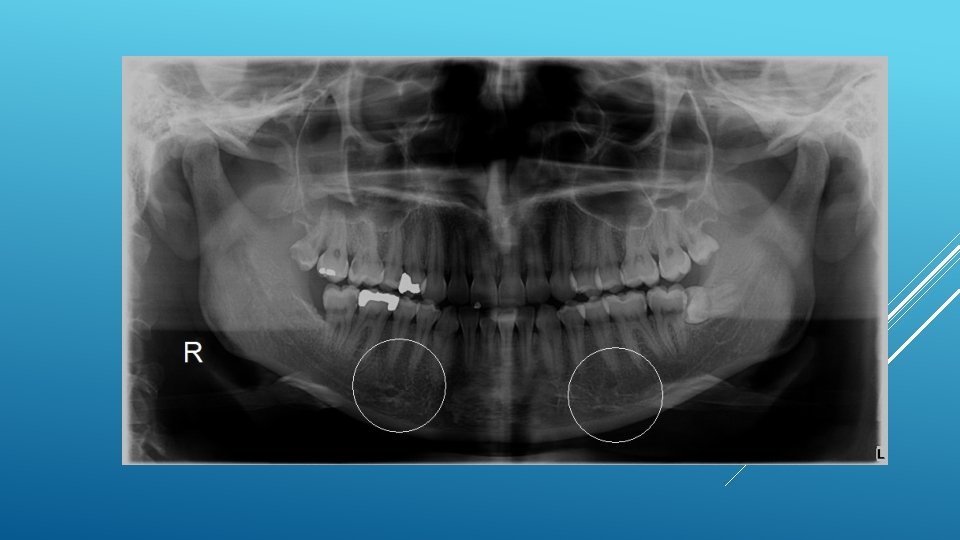

LOCATION AND DIMENSIONS OF THE MENTAL FORAMEN: A RADIOGRAPHIC ANALYSIS BY USING CONE-BEAM COMPUTED TOMOGRAPHY The majority of MF (56%) were located apically between the 2 premolars, and another 35. 7% of MF were positioned below the second premolar. On average, the MF was localized 5. 0 mm from the closest root of the adjacent tooth (range, 0. 3 -9. 8 mm). The mean size of the MF showed a height of 3. 0 mm and a length of 3. 2 mm; however, individual cases showed large differences in height (1. 8 -5. 1 mm) and in length (1. 8 -5. 5 mm). All mental canals exiting the MF demonstrated an upward course in the coronal plane, with 70. 1% of the mental canal presenting an anterior loop (AL) in the axial view. The mean extension of AL in cases with an AL was 2. 3 mm.

RELATIONSHIP BETWEEN THE POSITION OF THE MENTAL FORAMEN AND THE ANTERIOR LOOP OF THE INFERIOR ALVEOLAR NERVE AS DETERMINED BY CONE BEAM COMPUTED TOMOGRAPHY COMBINED WITH MIMICS The parameters were measured, and their values include mean (SD) anterior loop length, 1. 16 (1. 78) mm; anterior loop angle, 19. 13 (26. 89) degrees; inferior alveolar canal diameter, 3. 01 (0. 67) mm; height of the inferior alveolar canal, 10. 32 (1. 56) mm; 2 -dimensional mental foramen diameter, 2. 97 (0. 61) mm; 3 D mental foramen diameter, 2. 95 (0. 59) mm; 2 -dimensional vertical height of the mental foramen, 14. 67 (1. 67) mm; and 3 D vertical height of the mental foramen, 14. 61 (1. 69) mm. The mental foramen was located apically between the first and second premolars in 51. 67% and below the second premolar in 40. 83% of the cases.

THE MENTAL FORAMEN OR "THE CROSSROADS OF THE MANDIBLE. " AN ANATOMIC AND CLINICAL OBSERVATION] [ARTICLE IN FRENCH, GERMAN] THOMAS VON ARX 1 This paper presents a clinical and anatomical review of the mental foramen (MF) based on recent publications (since 1990). Usually, the MF is located below the 2 nd premolar or between the two premolars, but it may also be positioned below the 1 st premolar or below the mesial root of the 1 st molar. At the level of the MF, lingual canals may join the mandibular canal (hence the term "crossroads"). Accessory MF are frequently described in the literature with large ethnic variations in incidence. The emergence pattern of the mental canal usually has an upward and posterior direction. The presence and extent of an "anterior loop" of the mental canal may be overestimated with panoramic radiography. Limited cone-beam computed tomography currently appears to be the most precise radiographic technique for assessment of the "anterior loop". The mental nerve exiting the MF usually has three to four branches for innervation of the soft tissues of the chin, lower lip, facial gingiva and mucosa in the anterior mandible. The clinician is advised to observe a safety distance when performing incisions and osteotomies in the vicinity of the MF.

ANATOMICAL RELATIONSHIP BETWEEN MENTAL FORAMEN, MANDIBULAR TEETH AND RISK OF NERVE INJURY WITH ENDODONTIC TREATMENT he root apex of the mandibular second premolar (70 %), followed by the first premolar (18 %) and then the first molar (12 %), was the closest to the MF. Ninetysix percent of root apices evaluated were >3 mm from the MF. An AL was present in 88 % of the cases. Conclusions: With regards to endodontic treatment, the risk of nerve injury in the vicinity of the MF would appear to be low. However, the high incidence of the AL highlights the need for clinicians to be aware and careful of this important anatomical feature.

ASSESSMENT OF MORPHOLOGICAL AND ANATOMICAL CHARACTERISTICS OF MENTAL FORAMEN USING CONE BEAM COMPUTED TOMOGRAPHY All mental foramina were visualized. Regarding location, 49. 2% of the MFs were located between first and second premolars, 7. 7 distal and 39. 7% coincident to the apex of the mandibular second premolar. The mean MF opening angle was 45. 4° on the right side, and 45. 9° on the left. There were no statistically differences between gender groups with regard to the opening angle degree